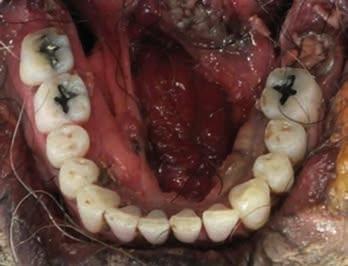

Dental Evidence Recovered: Maxilla and Mandible.

Frontal View

Right Left

Right Lateral View

Left Lateral View

Right Left Right Left

Maxilla

Mandible